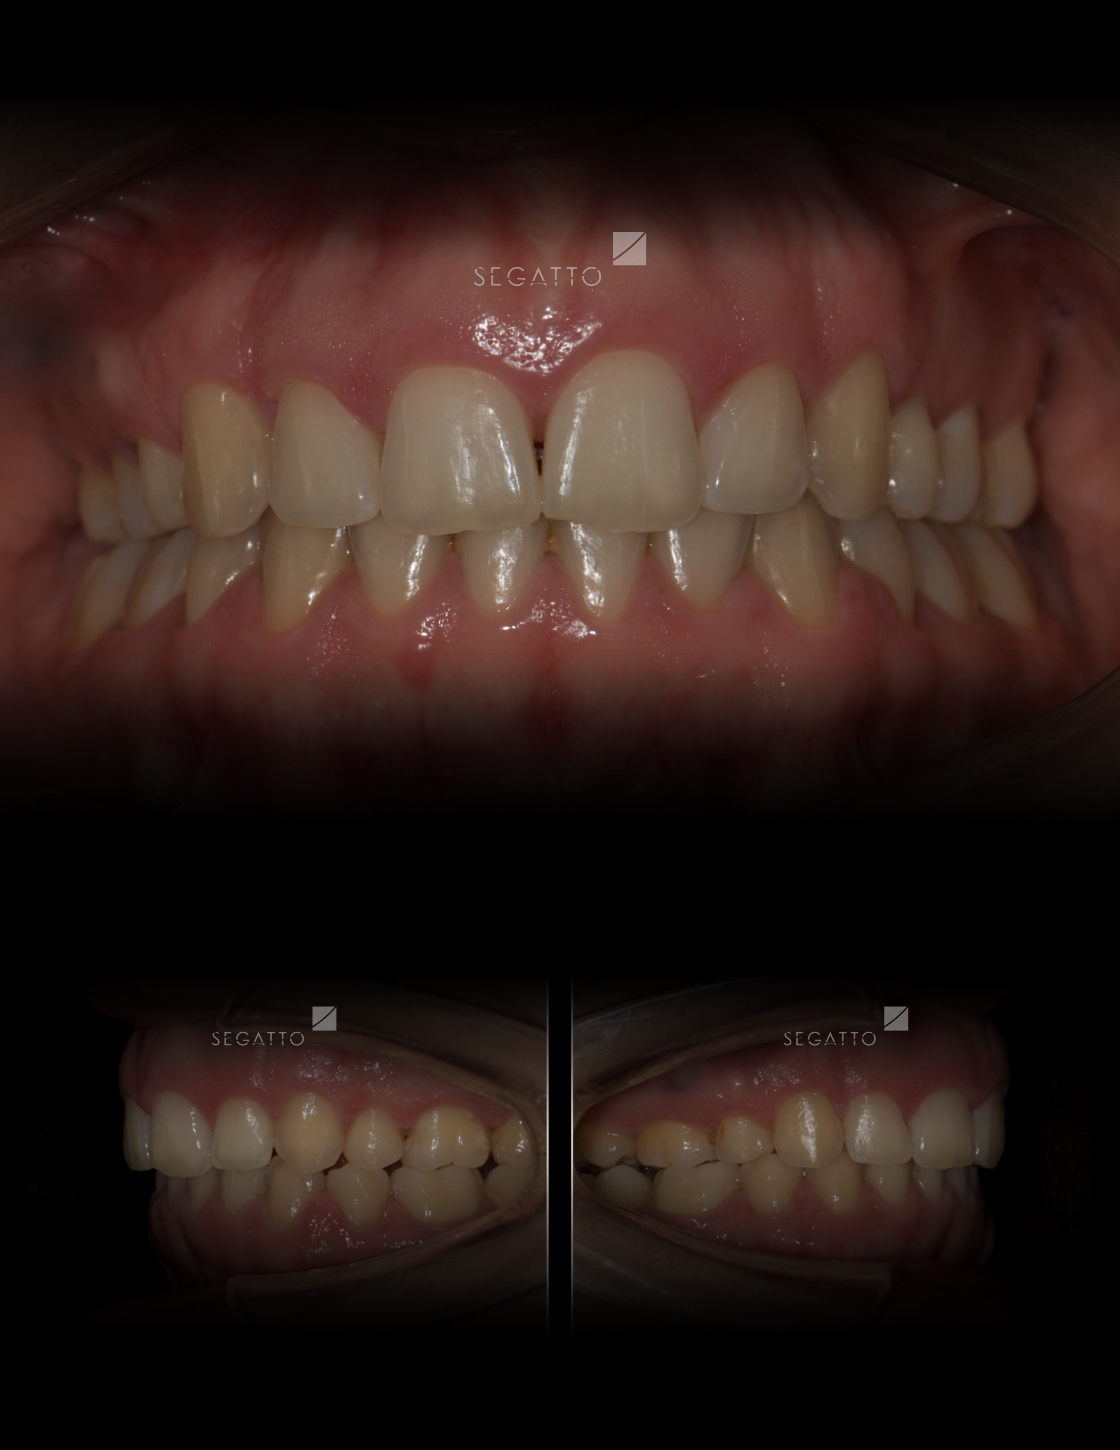

Orthodontics

Cases